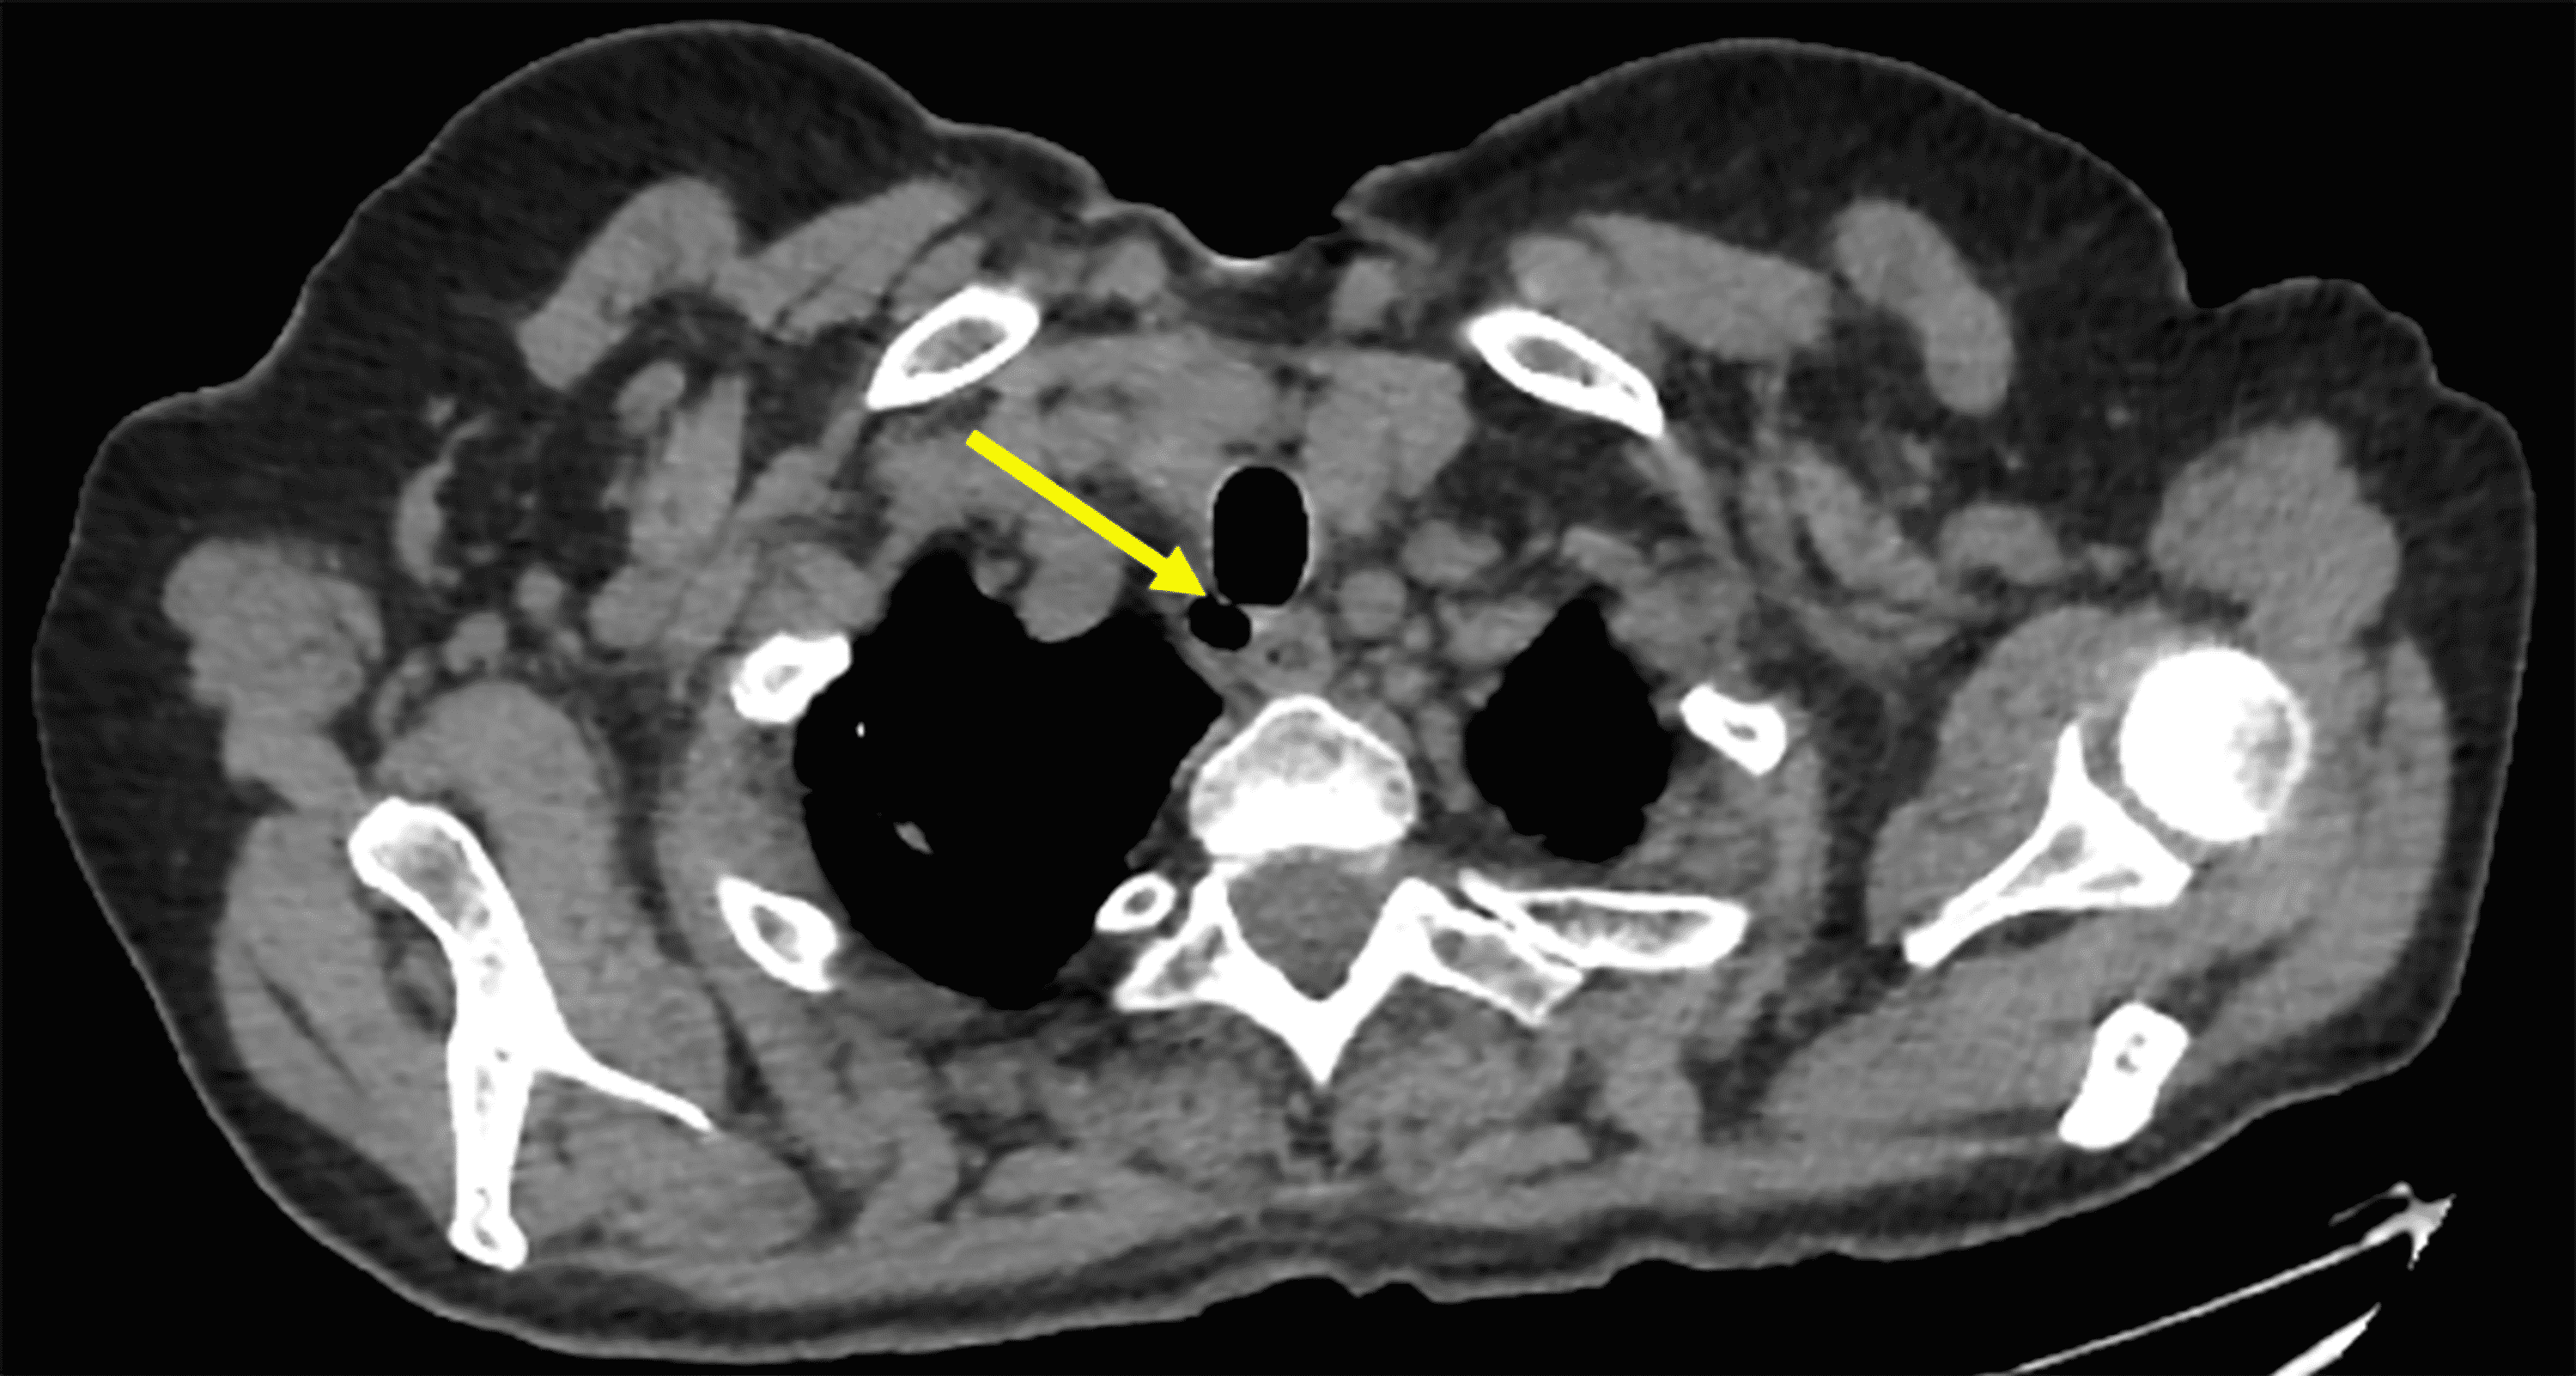

Tracheal Diverticulum Mimicking Pneumomediastinum A Case Report Tracheal Diverticulum Anesthesia Tracheal diverticula are rare congenital or acquired abnormalities of the posterior tracheal wall. This strategy should include risk assessment, planning and preparation. Tracheal extubation requires a clear strategy to avoid complications and keep patients safe. Tracheal diverticulum is a rare and often incidental diagnosis found on chest imaging in an asymptomatic patient with. Tracheal diverticula are extremely rare. Tracheal diverticulum. Tracheal Diverticulum Anesthesia.

From sumerdoc.blogspot.com

Tracheal DiverticulumCT Sumer's Radiology Blog Tracheal Diverticulum Anesthesia Tracheal diverticulum is a rare and often incidental diagnosis found on chest imaging in an asymptomatic patient with. Tracheal diverticulum (dv) is a type of paratracheal air cyst (ptac) that is often. Tracheal diverticula are rare congenital or acquired abnormalities of the posterior tracheal wall. Tracheal extubation requires a clear strategy to avoid complications and keep patients safe. This strategy. Tracheal Diverticulum Anesthesia.